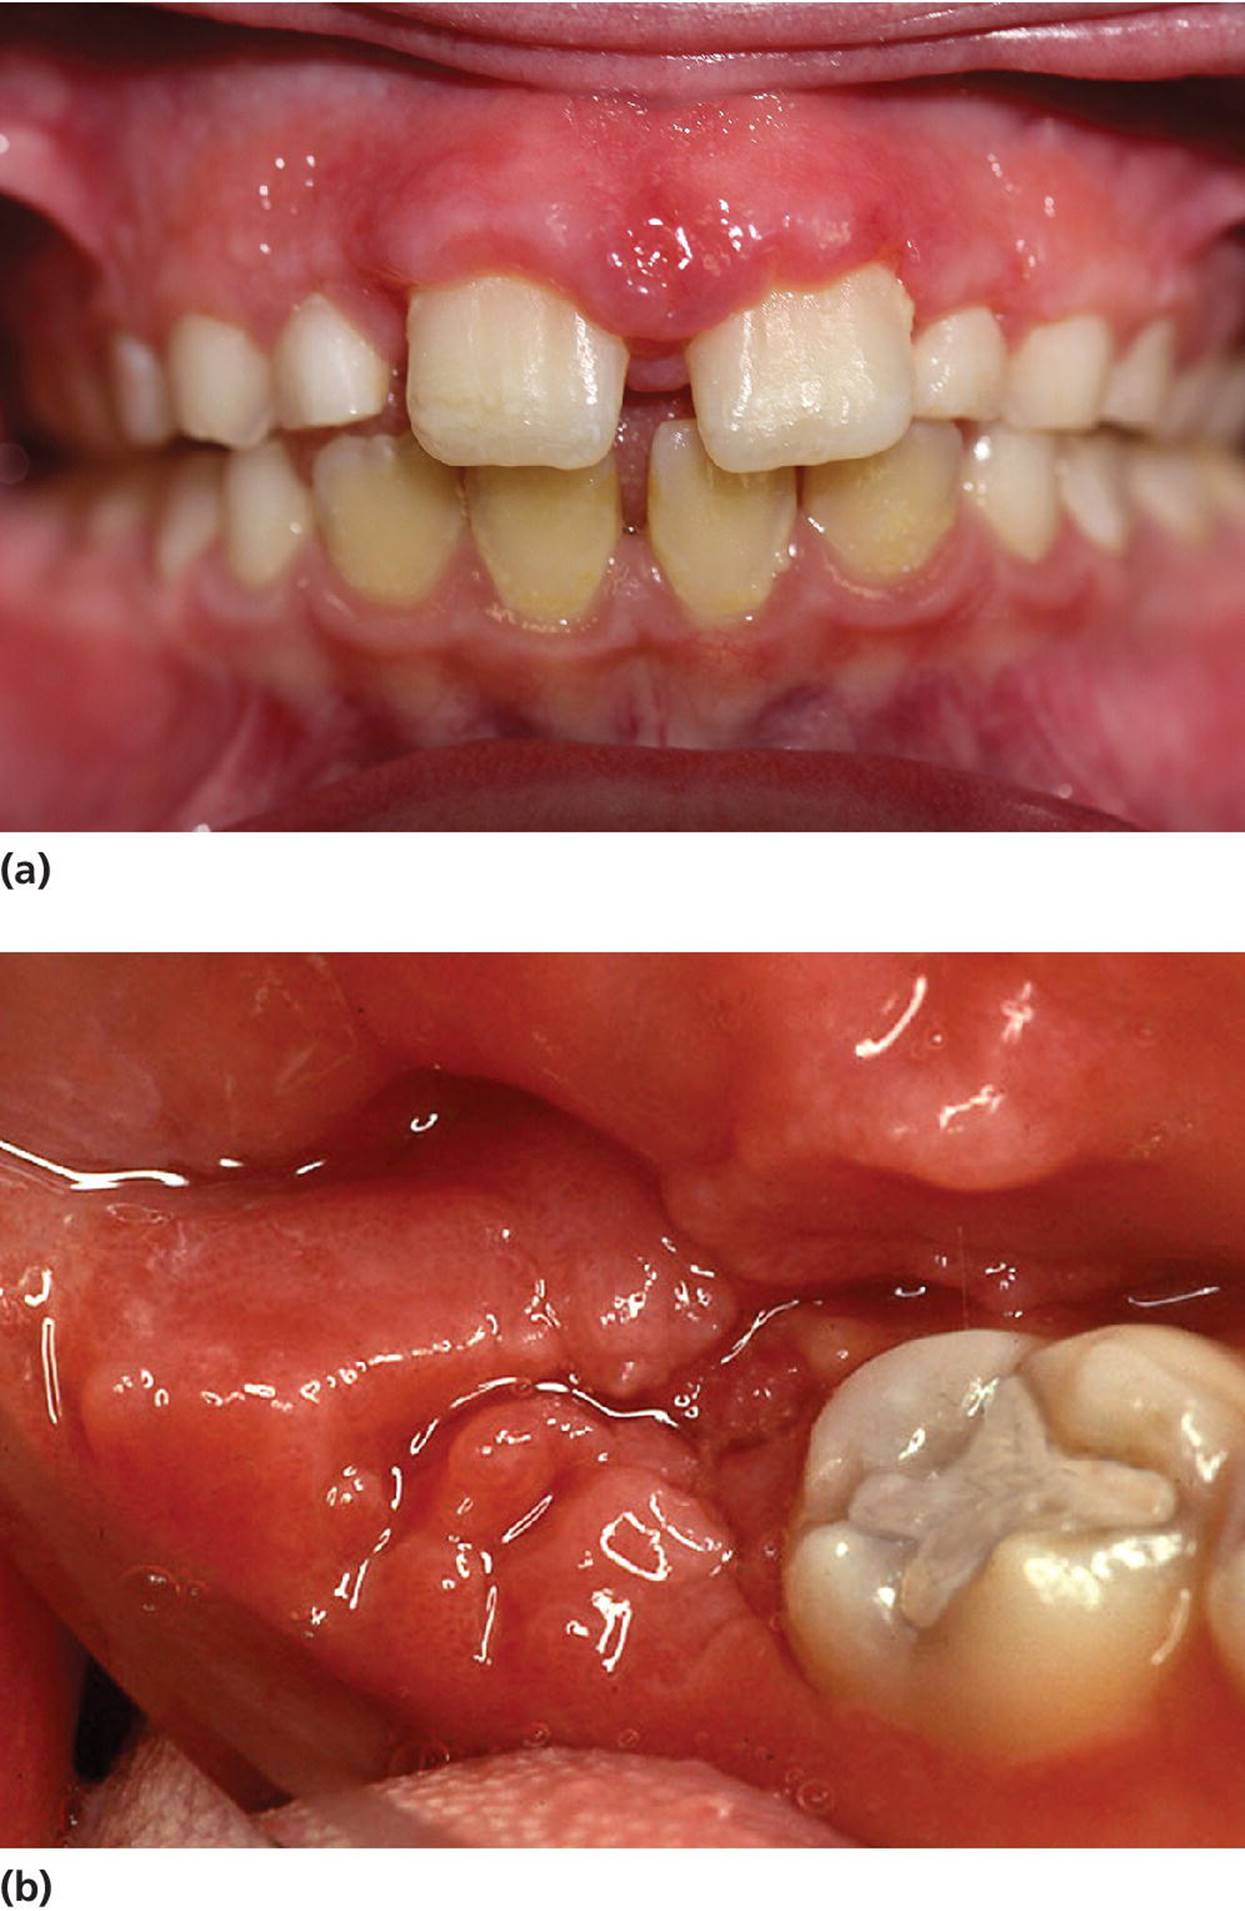

Crohn’s disease

Crohn’s disease is commonly associated with oral lesions. The lesions may also precede symptoms of bowel disease. The most common oral pathologic findings in Crohn’s disease are aphthous ulcers, areas of inflammatory hyperplasia, including mucosal fissuring and indurated “tag‐like” lesions on the retromolar area (Figure 15.14). The lesions tend to run a remitting course.

Figure 15.14 Crohn’s disease, gingival characteristics: (a) incisal region; (b) molar region.